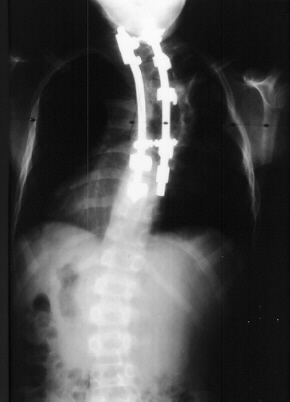

In preparation for spinal fusion for stabilization of this kyphoscoliosis he underwent a MRI of the brain cervical and thoracic spine and CT of the thorax. The brain and cervical spine showed no evidence of tumor. The lower cervical and upper thoracic canal was enlarged without evidence of cord compression, a finding consistent with dural ectasia . There is soft tissue protrusion into the thoracic canal that may resemble a dumbbell lesion.

Coinciding with current literature recommendations for treatment of severe dysplastic kyphoscoliosis, the patient underwent an Anterior-Posterior spinal fusion from T1-T10. The scoliosis was corrected to 21 degrees and kyphosis to 34 degrees. The procedure was augmented with a rib strut graft and was tolerated well. No neurologic complications occurred and the patient developed a solid fusion by one year without progression of the curvature. He is currently 5 years post-op playing in sports and without pain.